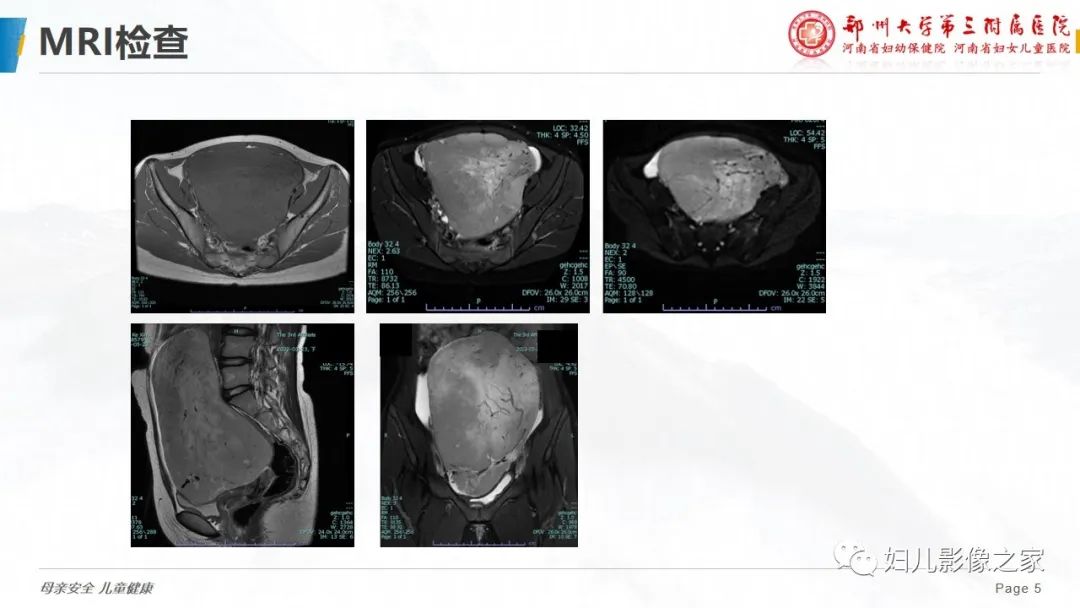

【病例】卵巢无性细胞瘤1例CT及MR影像-4